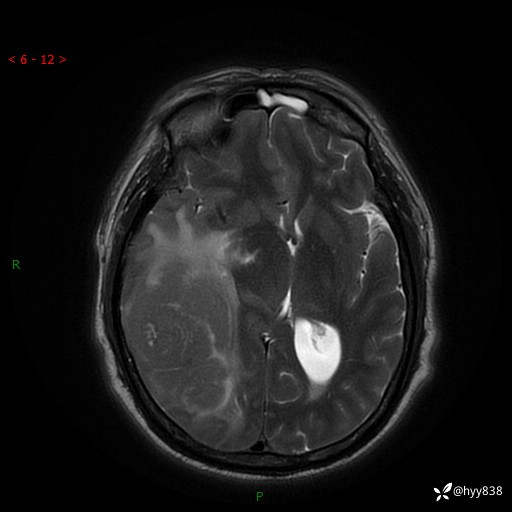

患者性别:男

患者年龄:56岁

简要病史:外院CT提示脑膜瘤,为进一步诊治来我院

辅助检查:MRI

临床诊断:颅脑占位

讨论:病变性质?

颅脑MRI平扫+增强